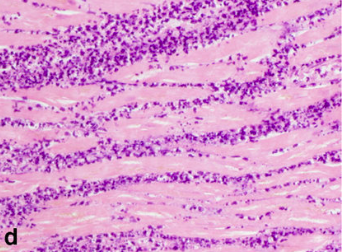

When would this histopatholigcal slide from an MI likely to have occurred

Less than 1 day

Less than 7 days

1-3 week granulation occurring

3-6 weeks